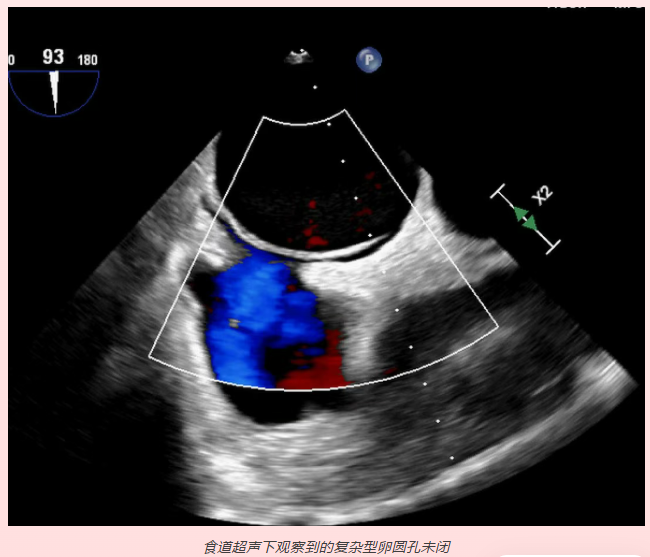

1.房间隔缺损(包括卵圆孔未闭)常规经胸超声不能确诊的病例,尤其对于怀疑有右向左分流导致脑卒中、脑梗塞的患者。